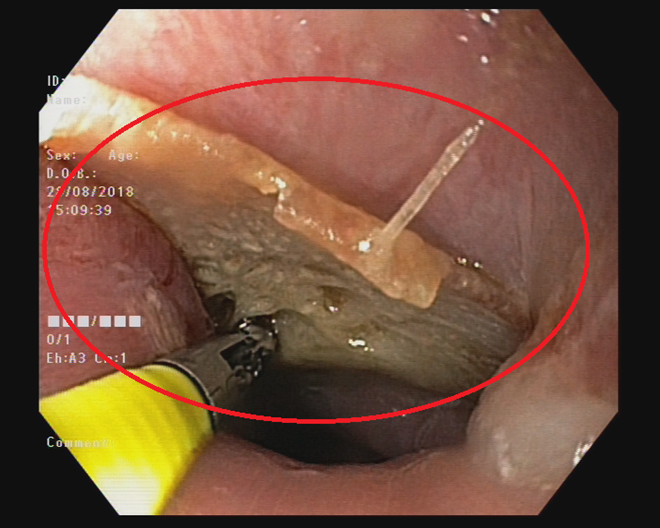

Ngày 28-8-2018, Trung tâm Nội Soi Bệnh  viện (BV) Đa khoa Xuyên Á – Vĩnh Long (BVXA – VL) cho biết, họ vừa xử trí thành công nội soi cấp cứu cho bệnh nhân T. (46 tuổi, ngụ tại huyện Cái Bè, tỉnh Tiền Giang) bị hóc mảnh xương cá Chẽm đúng vào phút giây quá mừng rỡ khi chứng kiến bàn thắng của U23 Việt Nam sút tung lưới U23 Syria.